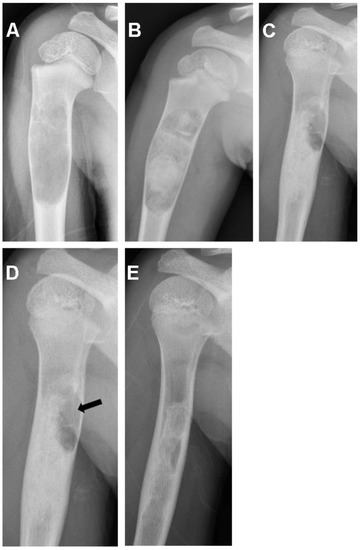

| 2/F/8 | Humerus | Simple bone cyst | 4.12 |